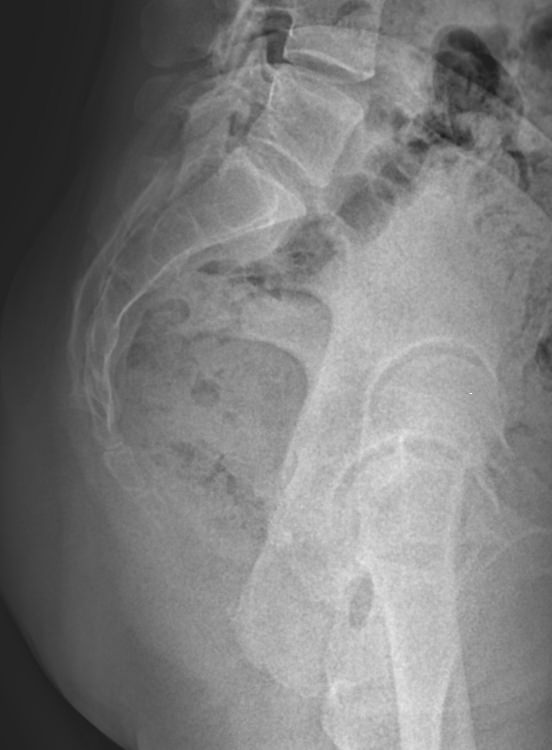

• Отклонение копчика кпереди по отношению к крестцу;

• Изменения в крестцово-копчиковом суставе: уменьшение рентгеновской щели, субхондральный склероз;

• Переломы;

• Новообразования.